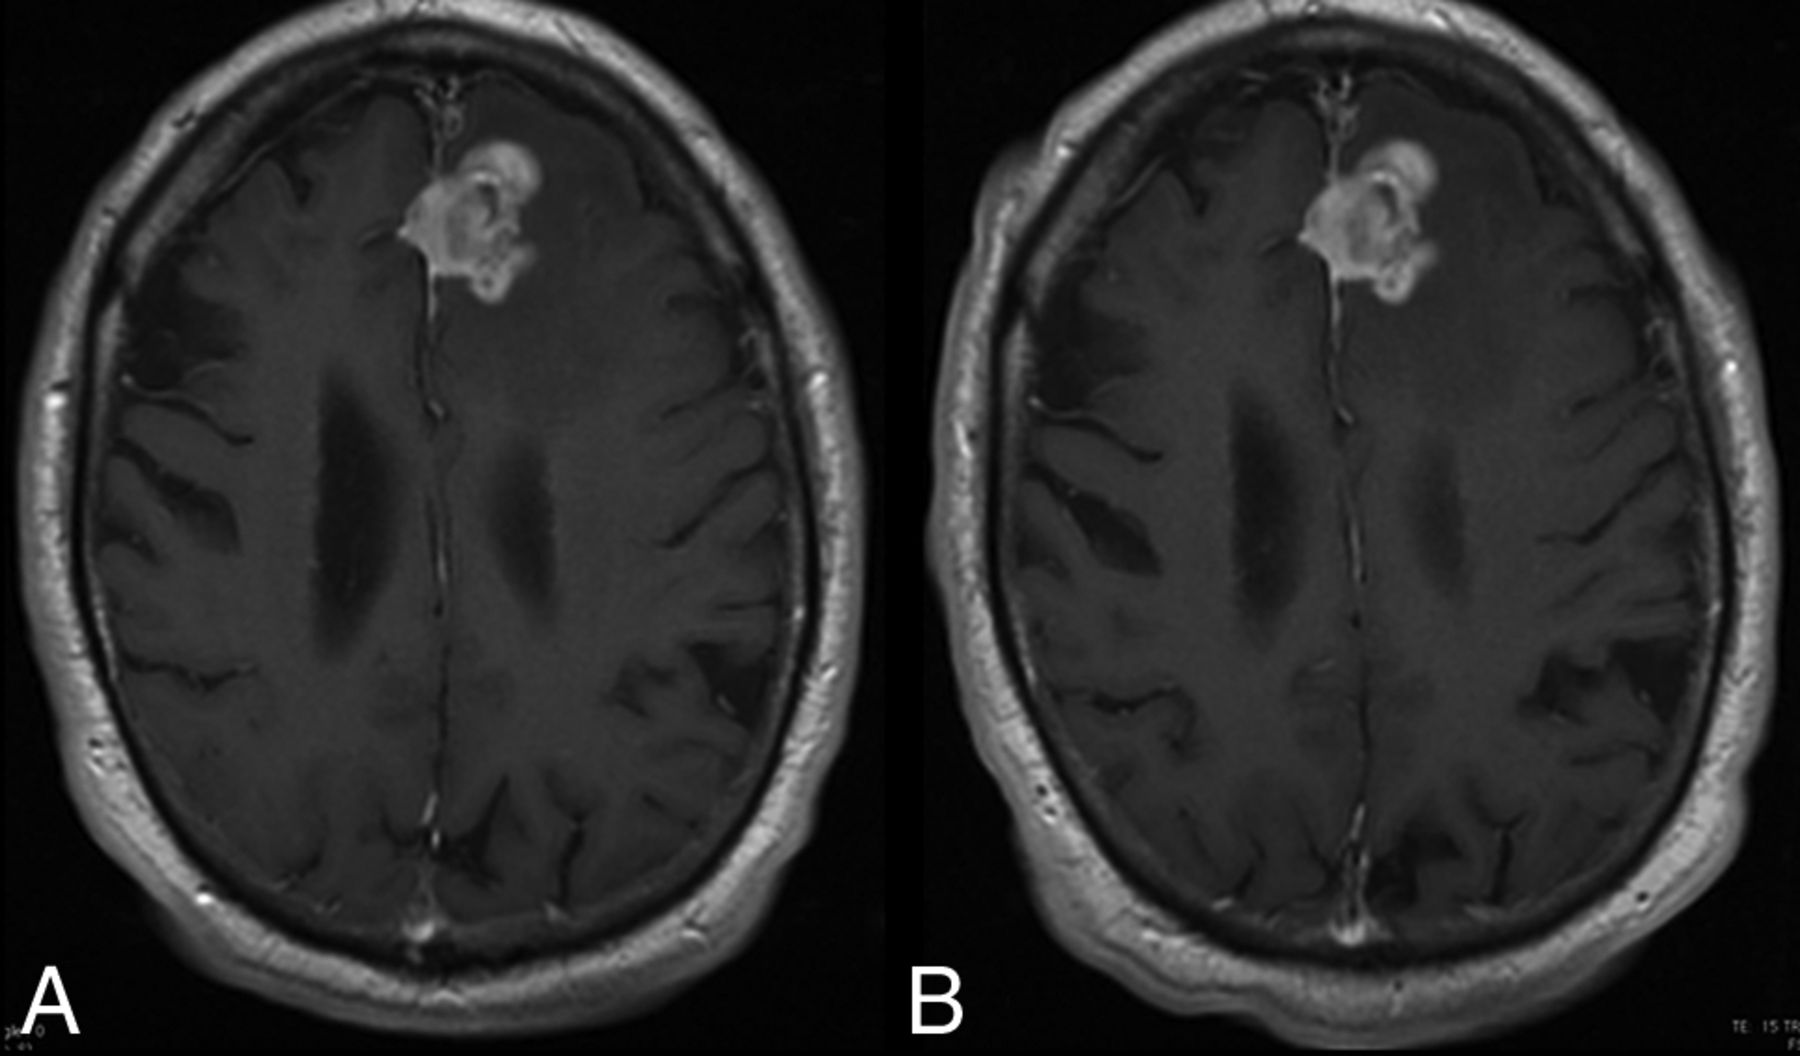

Figures 3 and 4 illustrate 2 case examples that demonstrate the identical appearance in lesion visualization and characterization observed for the 2 contrast agents.

A 74-year-old man with a high-grade glioma. T1 spin-echo images (1.5T) after administration of 0.1 mmol/kg of gadoterate meglumine (A) and gadobutrol (B) show an approximate 30-mm mass. The time between the 2 MR imaging examinations was 8 days. Lesion visualization and characterization were scored as excellent by all 3 blinded readers. The mass is clearly seen on both examinations and shows no difference in contrast enhancement.